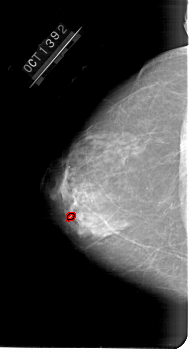

A_1647_1.LEFT_CC

LEFT_CC LINES 6691 PIXELS_PER_LINE 3586 BITS_PER_PIXEL 12 RESOLUTION 43.5 OVERLAY

FILE: A_1647_1.LEFT_CC.OVERLAY

TOTAL_ABNORMALITIES 1

ABNORMALITY 1

LESION_TYPE CALCIFICATION TYPE PLEOMORPHIC DISTRIBUTION CLUSTERED

ASSESSMENT 4

SUBTLETY 1

PATHOLOGY BENIGN

TOTAL_OUTLINES 1

BOUNDARY